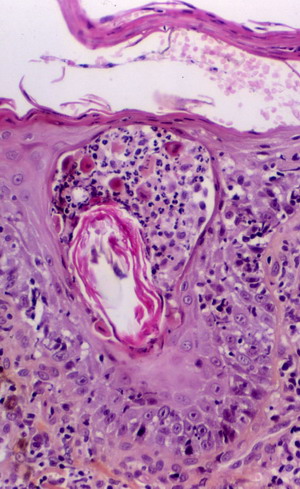

Enfin sur une section, l’attention est immédiatement attirée par la présence d’ une pustule située sur la paroi folliculaire. Celle-ci contient des polynucléaires neutrophiles et de nombreux acanthocytes.

Un cas de pemphigus érythémateux canin